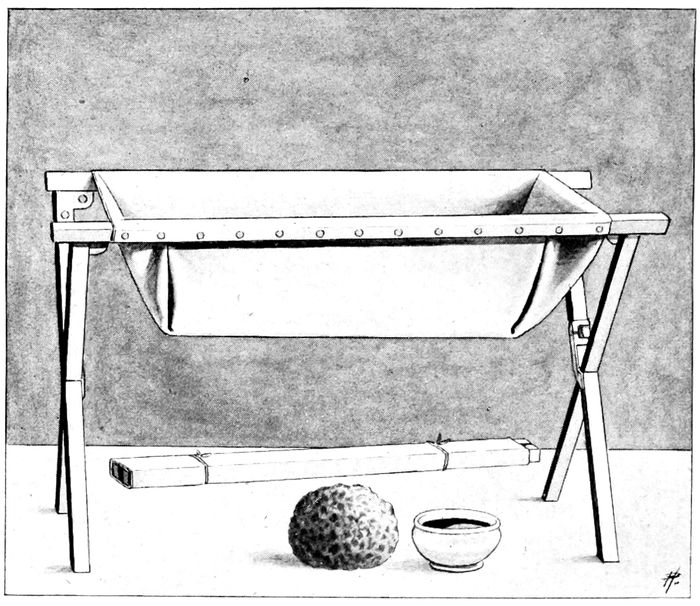

Rubber bath tub |

266 |